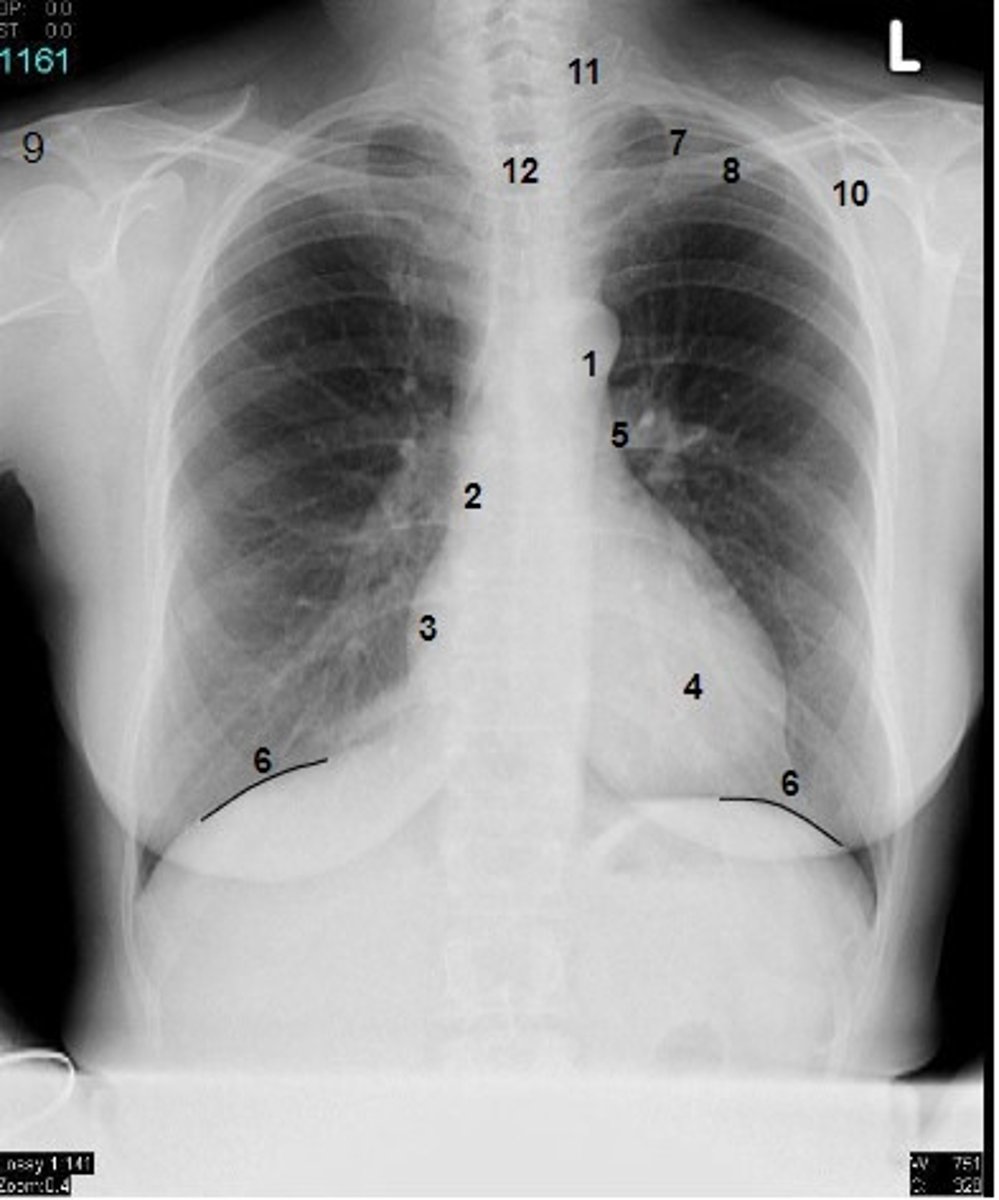

1

at what number is the arch of aorta?

2

at what number is the superior vena cava

3

at what number is the right atrium

4

at what number is the left ventricle

5

at what number is the primary bronchus

6

at what number is the dome of diaphragm

7

at what number is the first rib

8

at what number is the clavicle

9

at what number is the acromion of scapula

10

at what number is the coracoid process of scapula

11

at what number is the transverse process of vertebra

12

at what number is the spinous process of vertebra